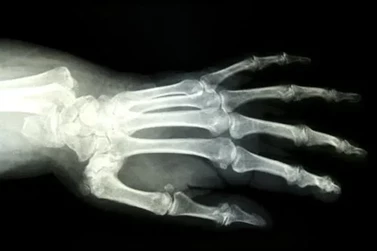

A scaphoid fracture is a break of the scaphoid bone in the wrist. This often happens as a result of a fall on an outstretched hand, where the impact of the fall forces the hand backward.